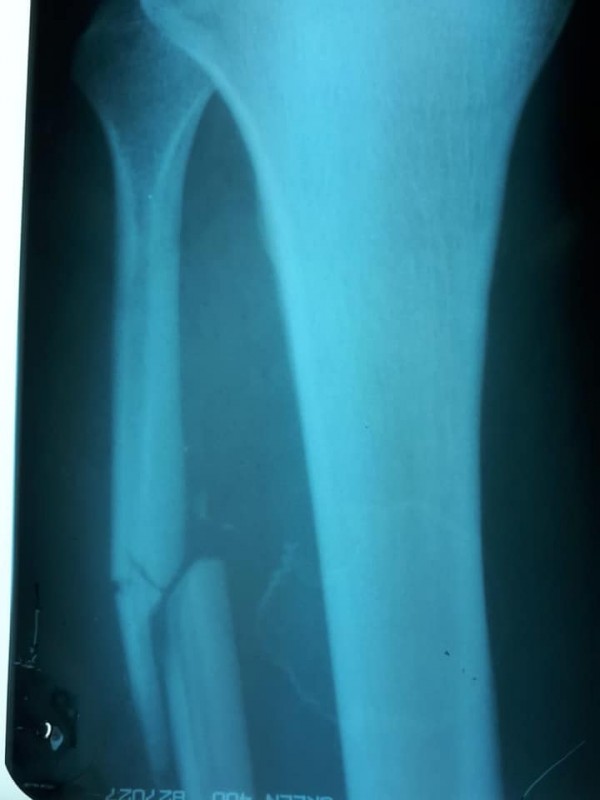

"Честно говоря, я лично думал, что ему просто "отсушили" бедро лоу-киками и гематома скоро спадет. Сегодня на рентгене, по возвращении на родину, выяснилось, что Алиби во втором бою сломал малую берцовую кость! Как можно с такой травмой даже просто ходить, а не биться и завоевать медаль на чемпионате мира - для меня загадка, удивление и восхищение!" - поделился Махметов.

По словам Махметова, у Алиби осколочный перелом со смещением берцовой кости. Спортсмену понадобится операция.